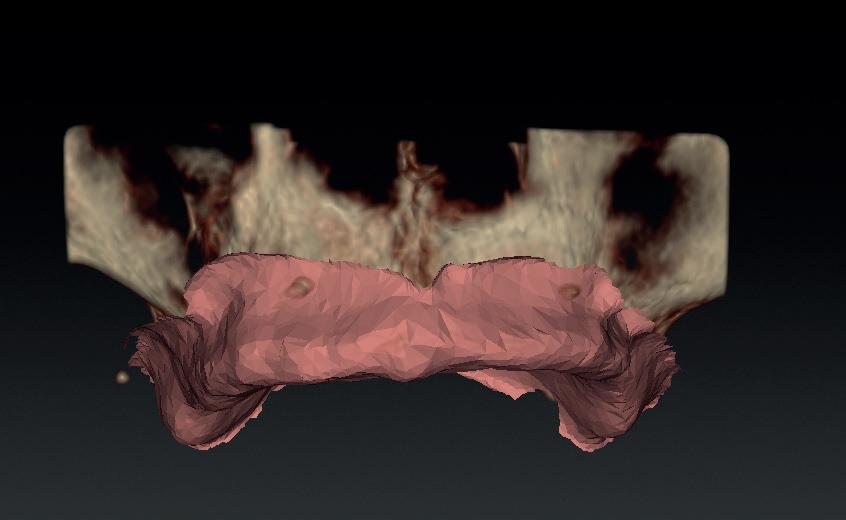

Voor het implantologisch onderzoek werd een CBCTscan (Trium CBCT, Acteon Frankrijk) vervaardigd van de edentate bovenkaak en in de software werd een planning gemaakt van 6 implantaten in de bovenkaak. De kaak kan opgedeeld worden in het front, tussen de 13 en 23 en de zijdelingse delen van de 14 t/m 17 en 24 t/m 27. Er dienen 2 implantaten in het front geplaatst te worden en 2 implantaten in de zijdelingse delen rechts en links, om een optimale verdeling van de implantaten (implant spread) te krijgen. De implantaten in deze casus werden gepland op posities 12, 22, 14, 24, 16 en 27. Tevens werd rekening gehouden met de krachtenverdeling óp de implantaten, deze zijn naar dorsaal toe forser dan in het front, daarom werd er gekozen voor brede implantaten (meer dan 5.0 mm in diameter) distaal en 4.0 mm diameter implantaten in het front. Voor de 16 was een crestale sinusbodemelevatie nodig en de 14 benodigde een kaakverbreding en verhoging.

Om de implantaten op de juiste vooraf geplande positie te implanteren, zijn er een aantal mogelijkheden (afbeelding 1 en 2). Eén daarvan is om de chirurgie guided uit te voeren, maar dat is lastig omdat de guide niet op elementen afgesteund kan worden. De guide dient dan met guide pins vastgeschroefd te worden, maar dat heeft als nadeel dat bij verplaatsing van de guide de implantaten niet op de juiste positie staan. Bij immediaat implanteren kan tegenwoordig gebruikgemaakt worden van meerdere stac-

1. Edentate maxilla

2. Planning in de CBCT-software Acteon AIS